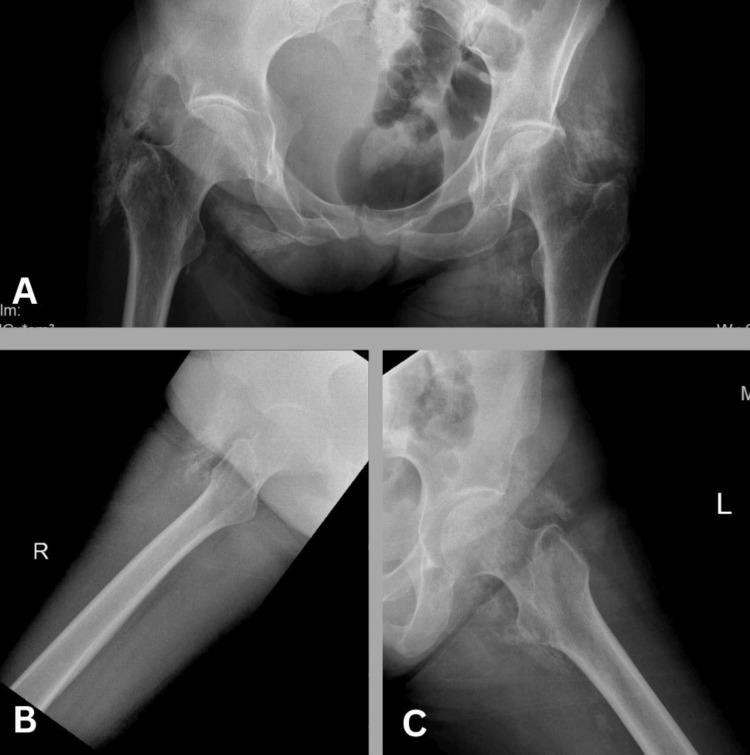

Positron emission tomography/computed tomography (PET/CT) using 18F-fluorodeoxyglucose ([18F]-FDG) is a widely adopted imaging modality for detecting hypermetabolic lesions. However, emerging positron-emitting tracers, such as radiopharmaceuticals featuring fibroblast activation protein (FAP) inhibitors (FAPI) labeled with [18F] or [68Ga], have opened new avenues in nuclear medicine. This case report focuses on the unique behavior of [68Ga]-FAPI in bilateral gluteal myositis ossificans, an infrequent condition characterized by soft tissue ossification. A 45-year-old woman with gastric adenocarcinoma underwent subtotal gastrectomy and received neoadjuvant and adjuvant chemotherapy; [68Ga]-FAPI PET revealed metastatic processes and unexpected [68Ga]-FAPI avid intramuscular ossifications in the pelvic and bilateral thigh muscles. Even though there was no history of trauma, the patient was diagnosed with myositis ossificans, a condition marked by non-cancerous ectopic ossifications. Diagnosis relies on history, radiology, and/or histology. FAPI imaging, increasingly used for inflammatory and infectious diseases, can exhibit uptake in benign conditions, including those involving bones and joints. This case report is the first to document incidental bilateral [68Ga]-FAPI uptake in bilateral gluteal myositis ossificans. The robust [68Ga]-FAPI activity in myositis ossificans highlights the importance of considering myositis ossificans in the context of soft tissue calcifications with intense [68Ga]-FAPI uptake.

使用18F-氟脱氧葡萄糖([18F]-FDG)的正电子发射断层扫描/计算机断层扫描(PET/CT)是一种广泛应用于检测高代谢病变的成像方式。然而,新出现的正电子发射示踪剂,如标记有[18F]或[68Ga]的成纤维细胞活化蛋白(FAP)抑制剂(FAPI)的放射性药物,为核医学开辟了新途径。本病例报告重点关注[68Ga]-FAPI在双侧臀肌骨化性肌炎中的独特表现,这是一种以软组织骨化为特征的罕见病症。一名45岁的胃腺癌女性患者接受了胃大部切除术,并接受了新辅助和辅助化疗;[68Ga]-FAPI PET显示有转移过程以及盆腔和双侧大腿肌肉中出现意外的[68Ga]-FAPI摄取增加的肌内骨化。尽管没有创伤史,但该患者被诊断为骨化性肌炎,这是一种以非癌性异位骨化为特征的病症。诊断依赖于病史、放射学和/或组织学检查。FAPI成像越来越多地用于炎症和感染性疾病,在包括涉及骨骼和关节的良性病症中也可表现出摄取增加。本病例报告首次记录了双侧臀肌骨化性肌炎中偶然出现的双侧[68Ga]-FAPI摄取。骨化性肌炎中强烈的[68Ga]-FAPI活性突出了在具有强烈[68Ga]-FAPI摄取的软组织钙化情况下考虑骨化性肌炎的重要性。